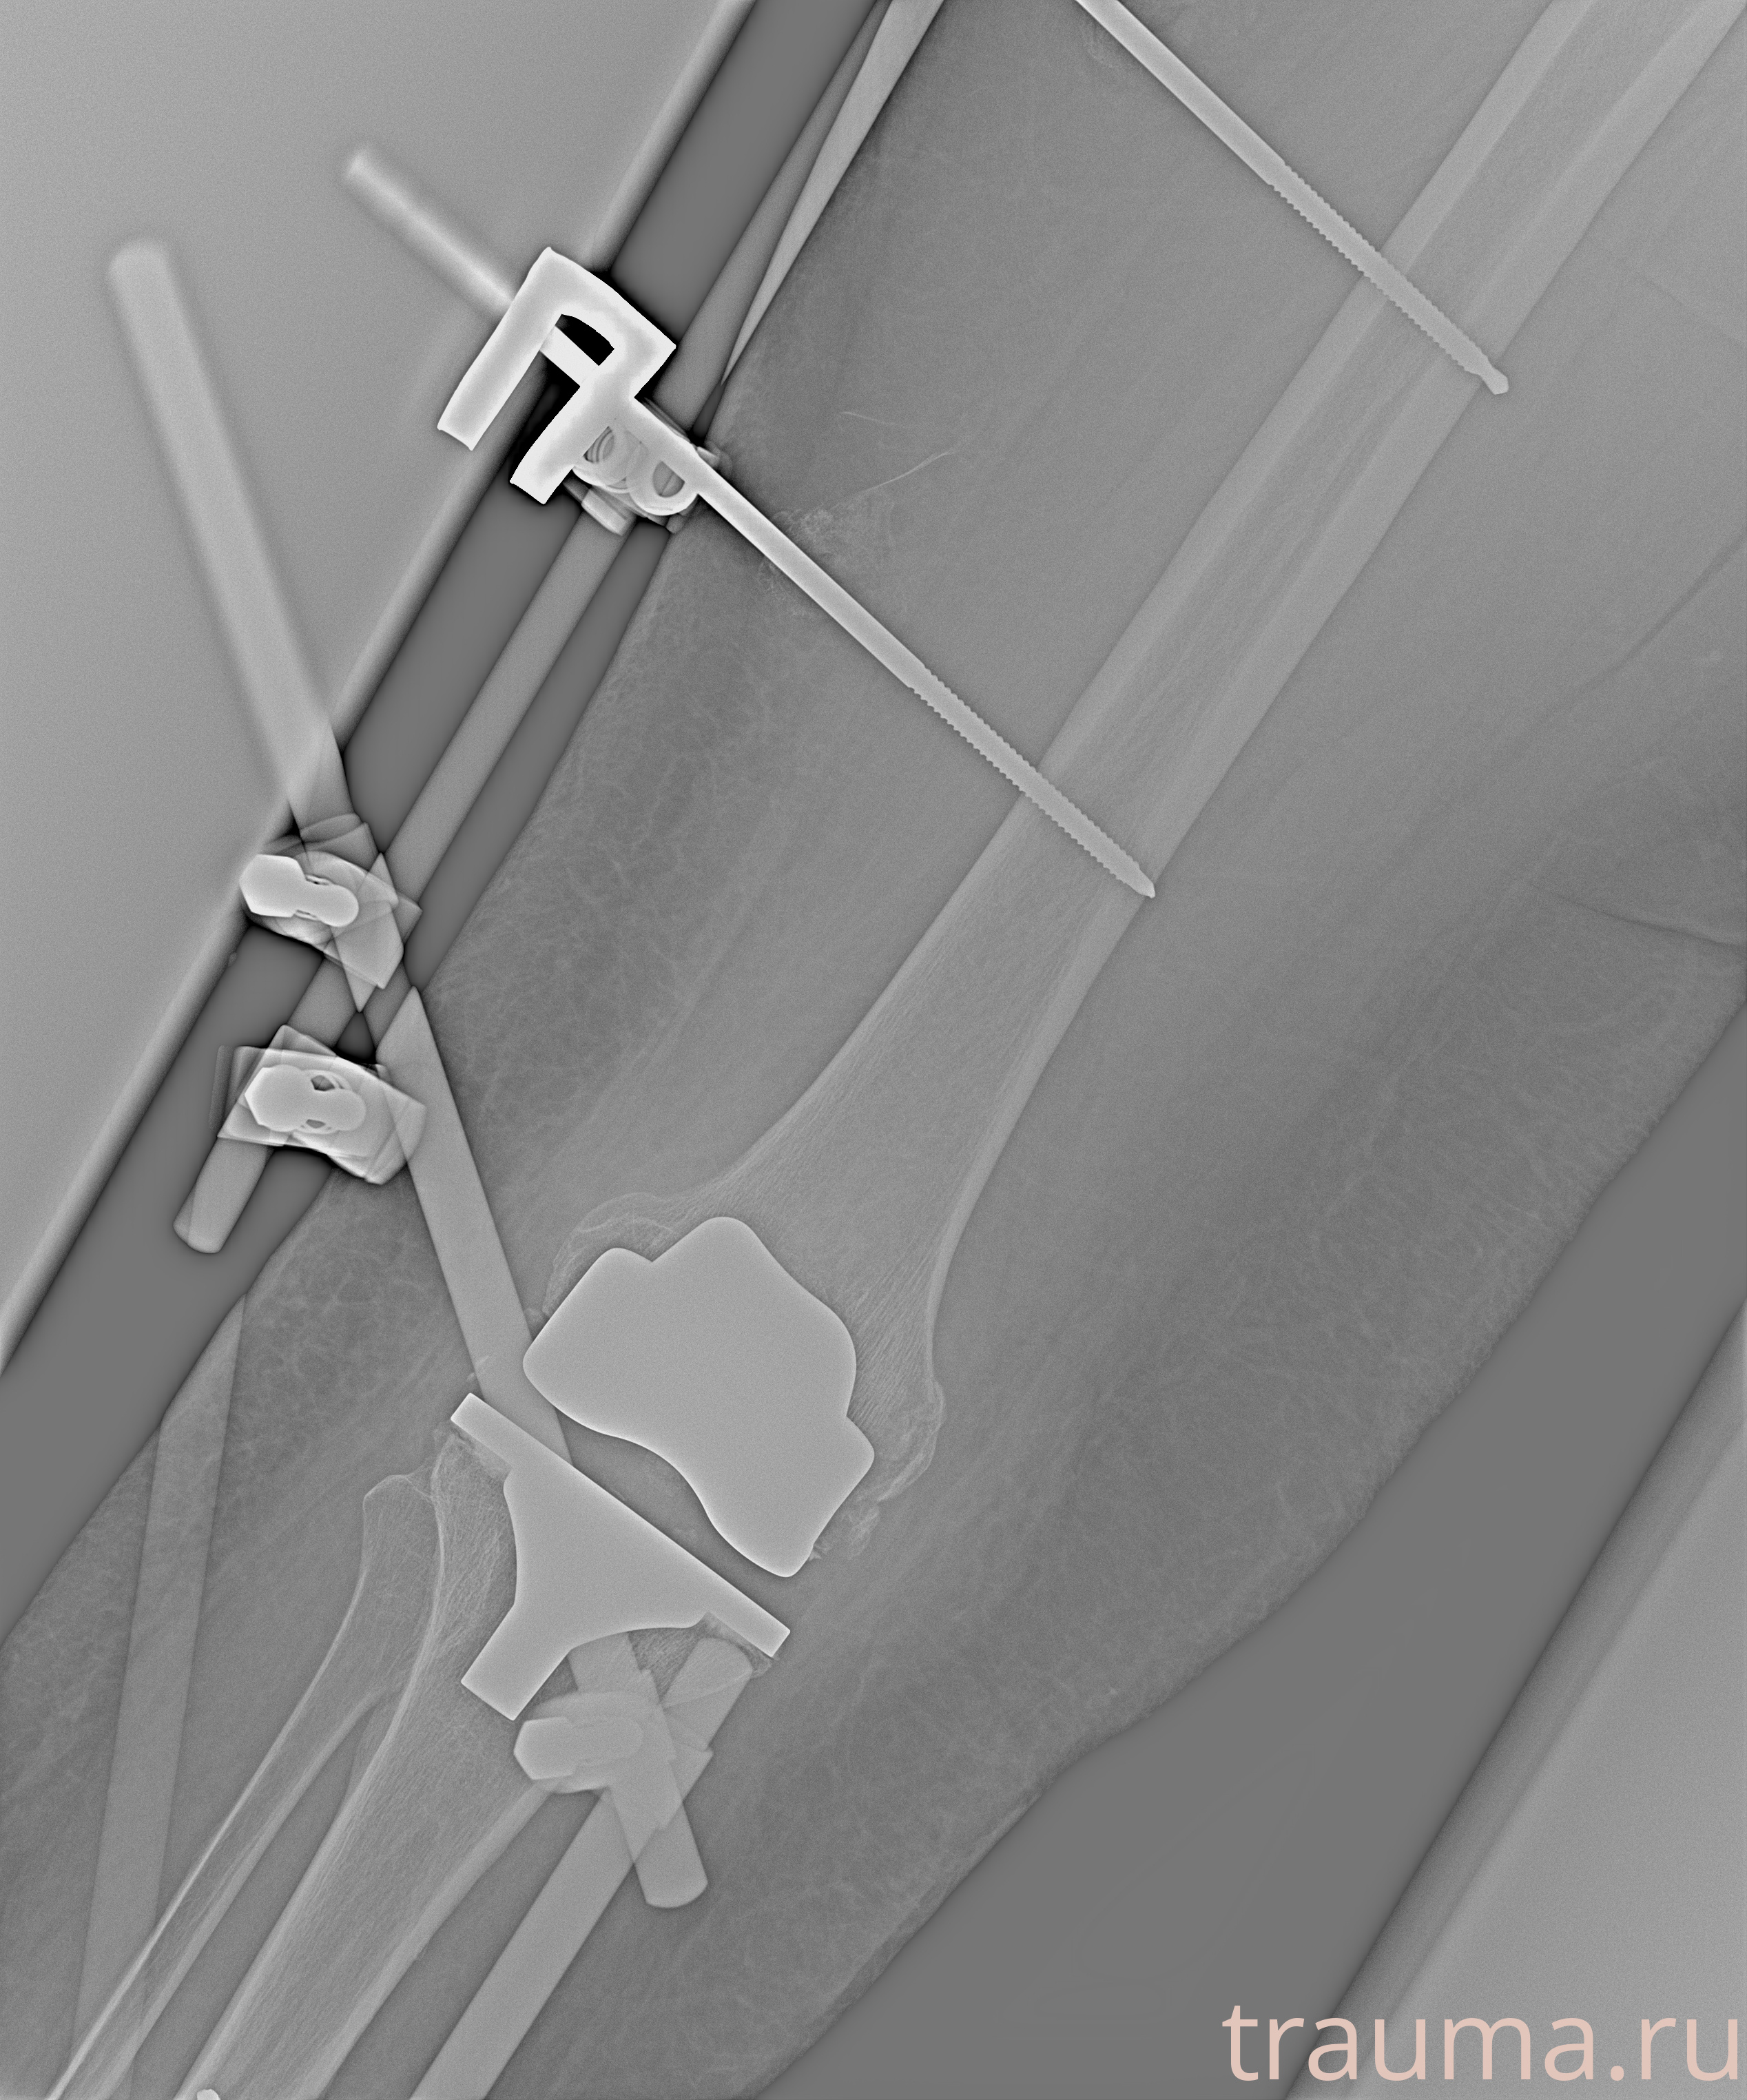

Рентгенограммы

Рентген на дому: по вашему адресу приезжает врач-рентгенолог, травматолог-ортопед с мобильным рентгеновским аппаратом, проводит диагностику травмы или заболевания, делает необходимые рентгенограммы, дает рекомендации по дальнейшему лечению. Получить качественные снимки в домашних условиях возможно благодаря уникальной методике, разработанной МосРентген Центром для института  Склифосовского